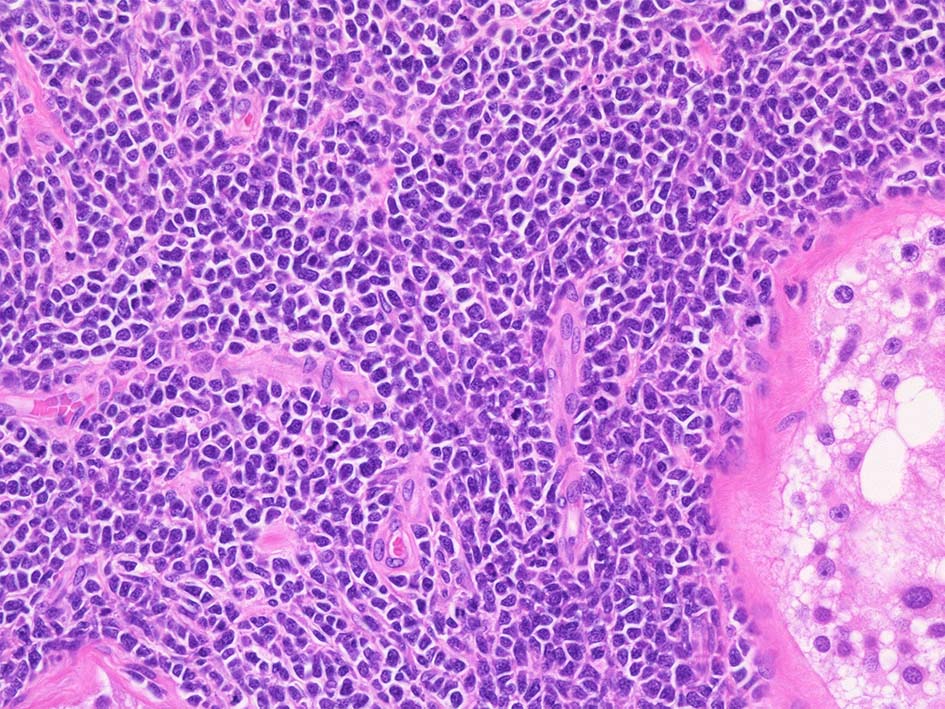

腫瘍内に壊死が認められる. 異型リンパ球の密な増殖により精細管は消失している.

腫瘍細胞はcentroblastic cells. mitosisやapoptosisが多い.

Diffuse large B-cell lymphoma of the lt. testis, 6.0x5.0x4.5cm in size.